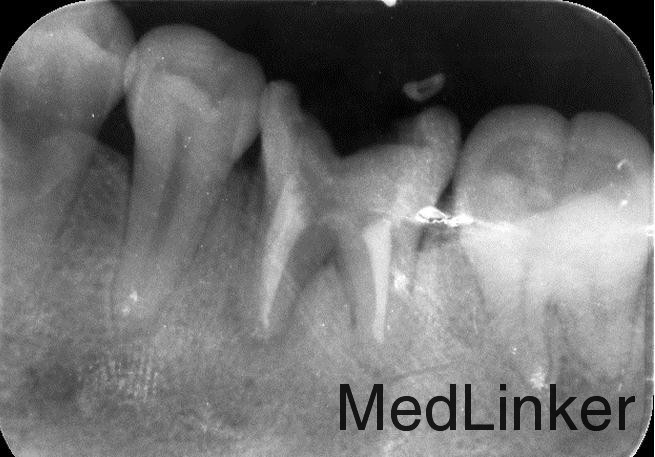

曲面断层片检查